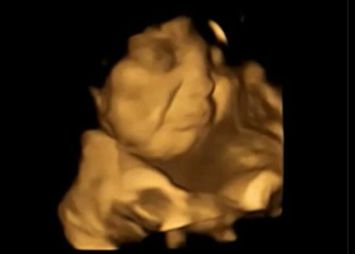

O echipă de oameni de știință a studiat ecografiile 4D a 100 de femei însărcinate și a descoperit că bebelușii expuși la arome de morcov au prezentat în mediul intrauterin reacții similare cu zâmbetul.

Cei expuși la arome de varză kale, în schimb, nu păreau să fie prea încântați și au fost surprinși afișând grimase.